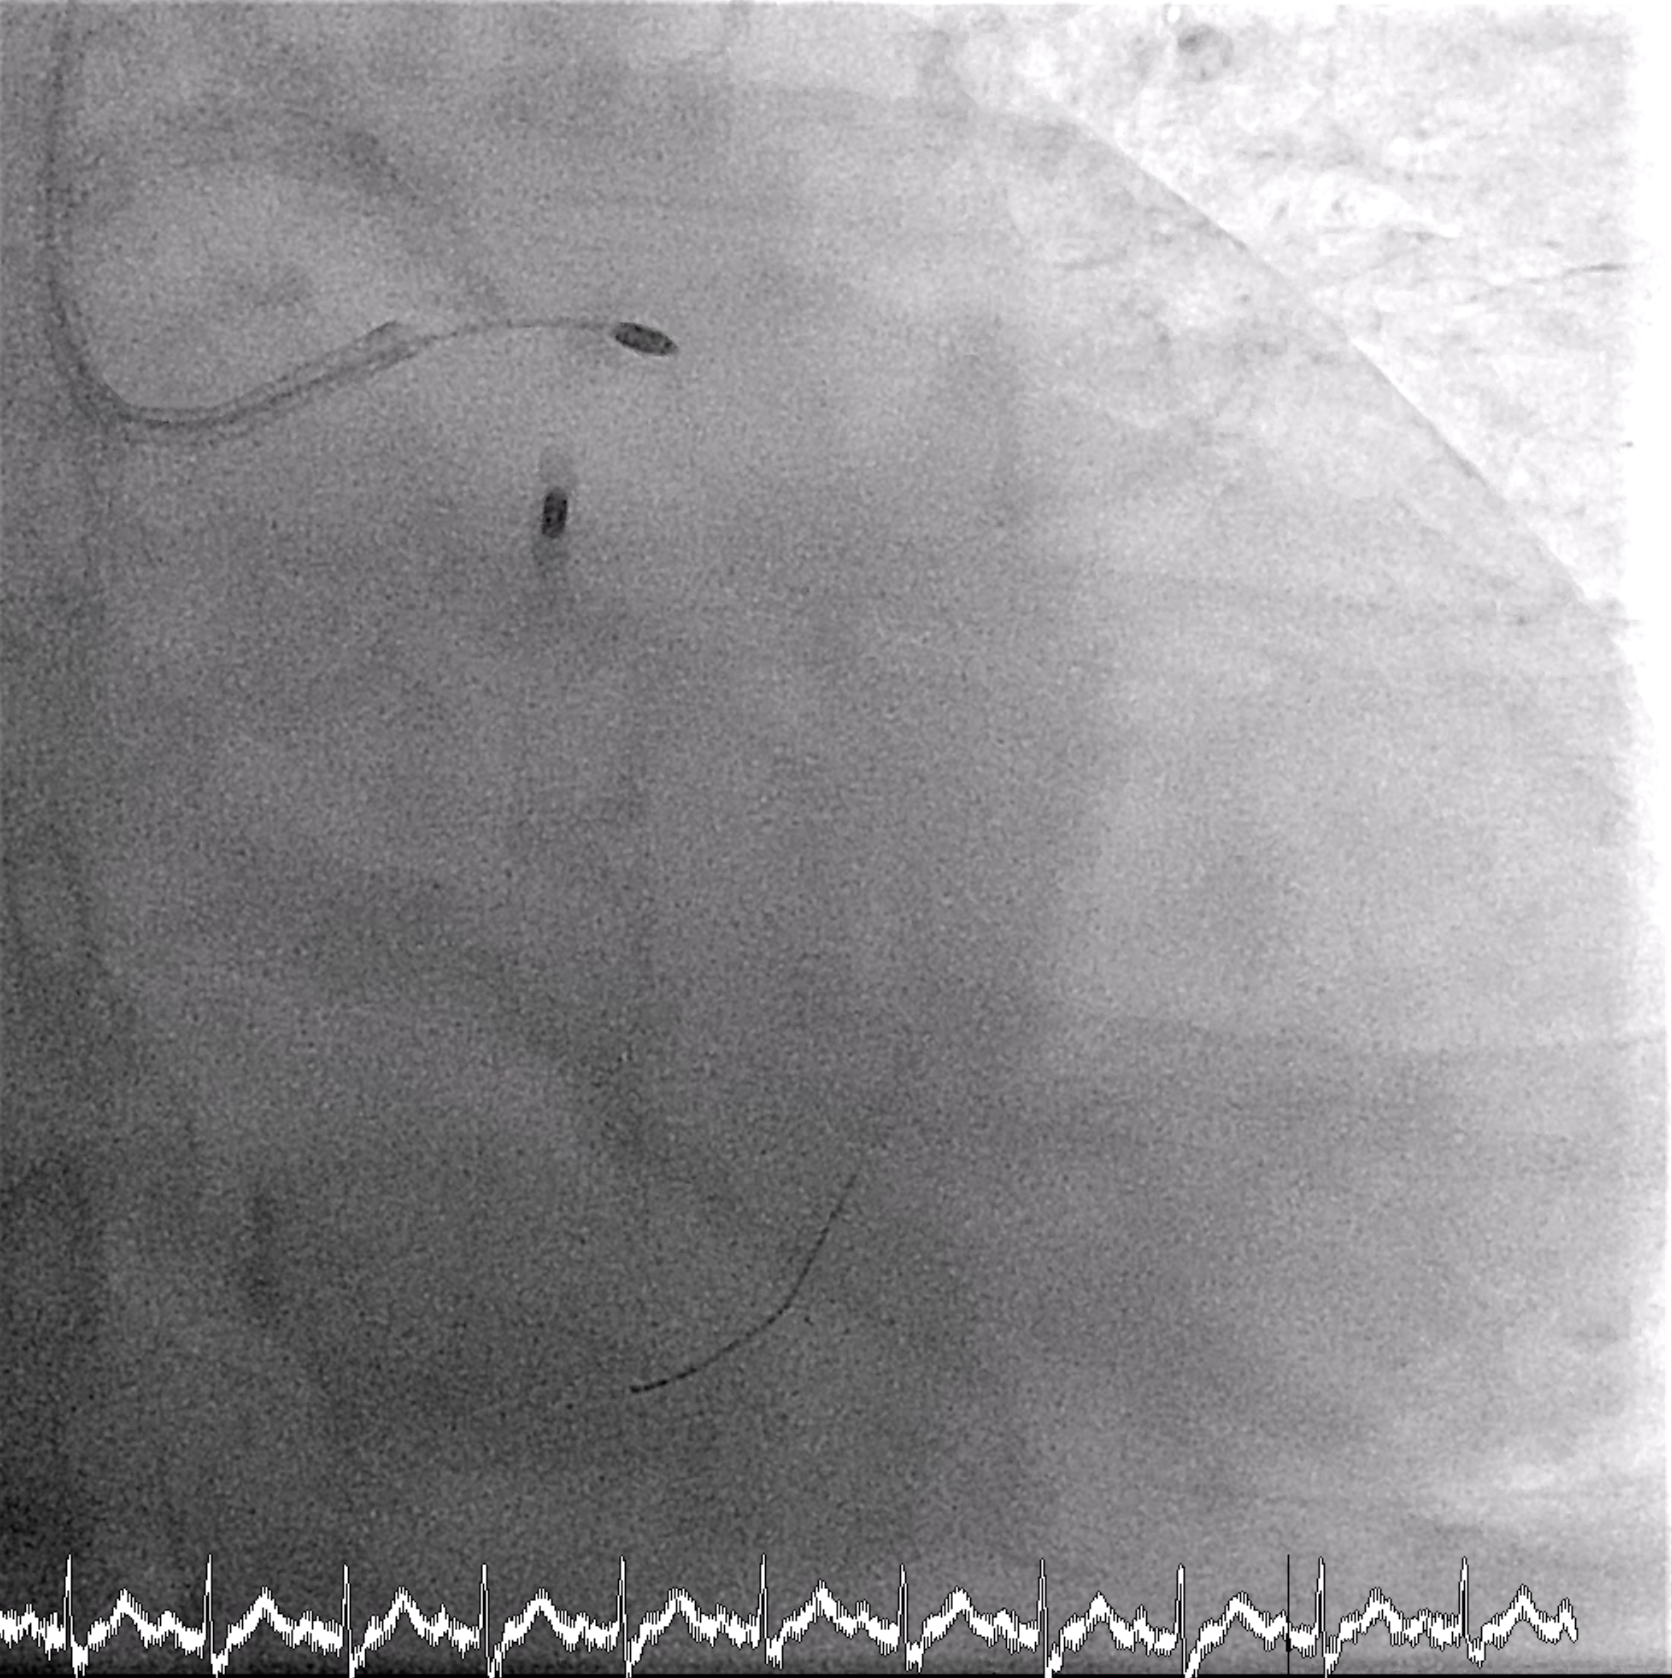

An 8 Fr IABP sheath was inserted via the right femoral artery under fluoroscopic guidance. The guidewire was advanced to the aortic root, and an ARROW IABP catheter was positioned in the descending aorta at the level of the aortic knob with good augmentation. Left femoral access was left for possible mechanical circulatory support. PCI was then initiated via right radial access using a 6/7 Fr APT sheath. The LMCA was engaged with an XB 3.5/7 GC, and an Anyreach wire was advanced to the LAD. IVUS could not cross the heavily calcified LM bifurcation, so rotational atherectomy was performed. After exchanging to a Rotadrive floppy wire, rotablation with a 1.75 mm burr was performed from LM to LAD for three runs at 147,000–166,000 rpm. POBA was carried out along LAD-D and LAD-P, followed by IVUS confirming circumferential calcification.Attention was then turned to the LCx. Due to uncrossable IVUS, the wire was exchanged for a Rotadrive floppy wire and rotablation was repeated from LM to LCx for seven runs at 136,000–166,000 rpm. Balloon dilation was performed, and IVUS again showed heavy LM–LCx calcification. A 3.0¡¿26 mm Frontier DES was placed from LM to LCx, followed by post-dilatation. Then a 3.0¡¿34 mm Frontier DES was deployed from LM to LAD-P, with sequential post-dilatation using NC balloons up to 18 atm. The bifurcation was optimized with rewiring and final kissing balloon inflation using 3.5 mm and 3.0 mm NC balloons, and proximal optimization with a 4.0 mm NC balloon.